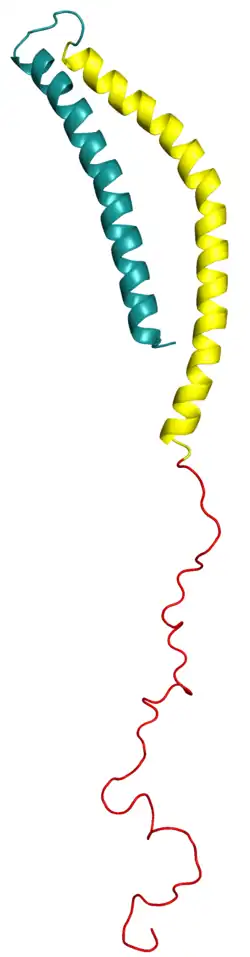

Alpha-synuclein pathology

.jpg)

Alpha-synuclein is an intracellular protein typically localized to presynaptic terminals and involved in synaptic vesicle trafficking, intracellular transport, and neurotransmitter release.[102][104] When misfolded, it can aggregate into oligomers and proto-fibrils that in turn lead to Lewy body formation.[104][105][106] Due to their lower molecular weight, oligomers and proto-fibrils may disseminate and be transmitted to other cells more rapidly.[106]

Lewy bodies consist of a fibrillar exterior and granular core. Although alpha-synuclein is the dominant proteinaceous component, the core contains mitochondrial and autophagosomal membrane components, suggesting a link with organelle dysfunction.[107][108] It is unclear whether Lewy bodies themselves contribute to or are simply the result of PD pathogenesis: alpha-synuclein oligomers can independently mediate cell damage, and neurodegeneration can precede Lewy body formation.[109]